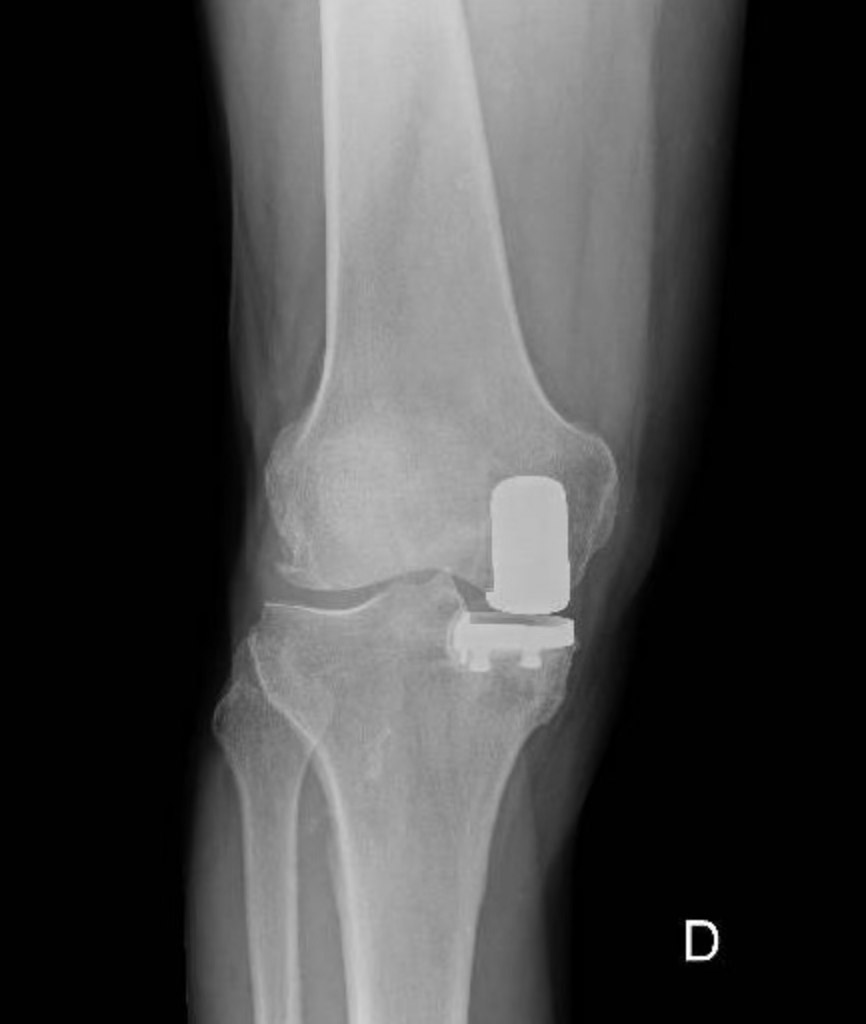

Protese parziale del ginocchio

La soluzione miniinvasiva che preserva i tuoi legamenti.

Le protesi parziali di ginocchio, note anche come protesi monocompartimentali, rappresentano una soluzione chirurgica avanzata per pazienti affetti da artrosi limitata a un singolo compartimento dell’articolazione. A differenza delle protesi totali, queste consentono di preservare i legamenti crociati anteriori e posteriori, mantenendo intatta la biomeccanica naturale del ginocchio.

Indicazioni per la Protesi Parziale:

Questa procedura è indicata per pazienti con artrosi limitata a un solo compartimento del ginocchio, con legamenti crociati intatti e senza deformità significative. Una valutazione clinica approfondita e l’uso di tecniche di imaging avanzate sono essenziali per determinare l’idoneità del paziente all’intervento.

Tecniche di Imaging Avanzate:

L’utilizzo di radiografie specifiche e, in casi selezionati, della risonanza magnetica nucleare (RMN) è fondamentale nella pianificazione preoperatoria. Le radiografie consentono di valutare l’estensione dell’artrosi e l’allineamento dell’arto, mentre la RMN offre una visione dettagliata delle strutture intra-articolari, come legamenti e cartilagine, assicurando una selezione accurata dei pazienti candidati alla protesi parziale.